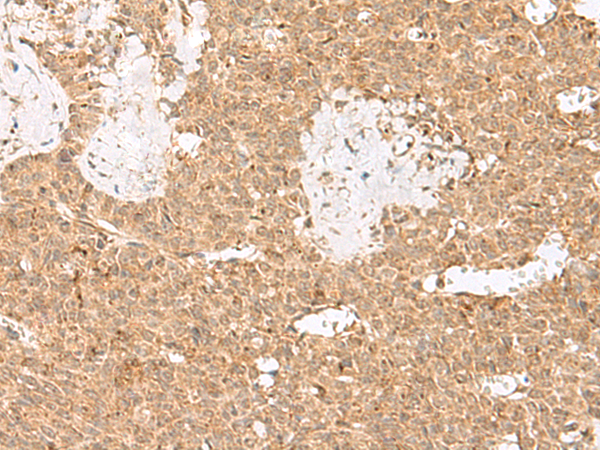

分类: 科研抗体货号: P13509别名: PSP24B; PSP24(beta)应用: IHC反应种属: Human, Mouse